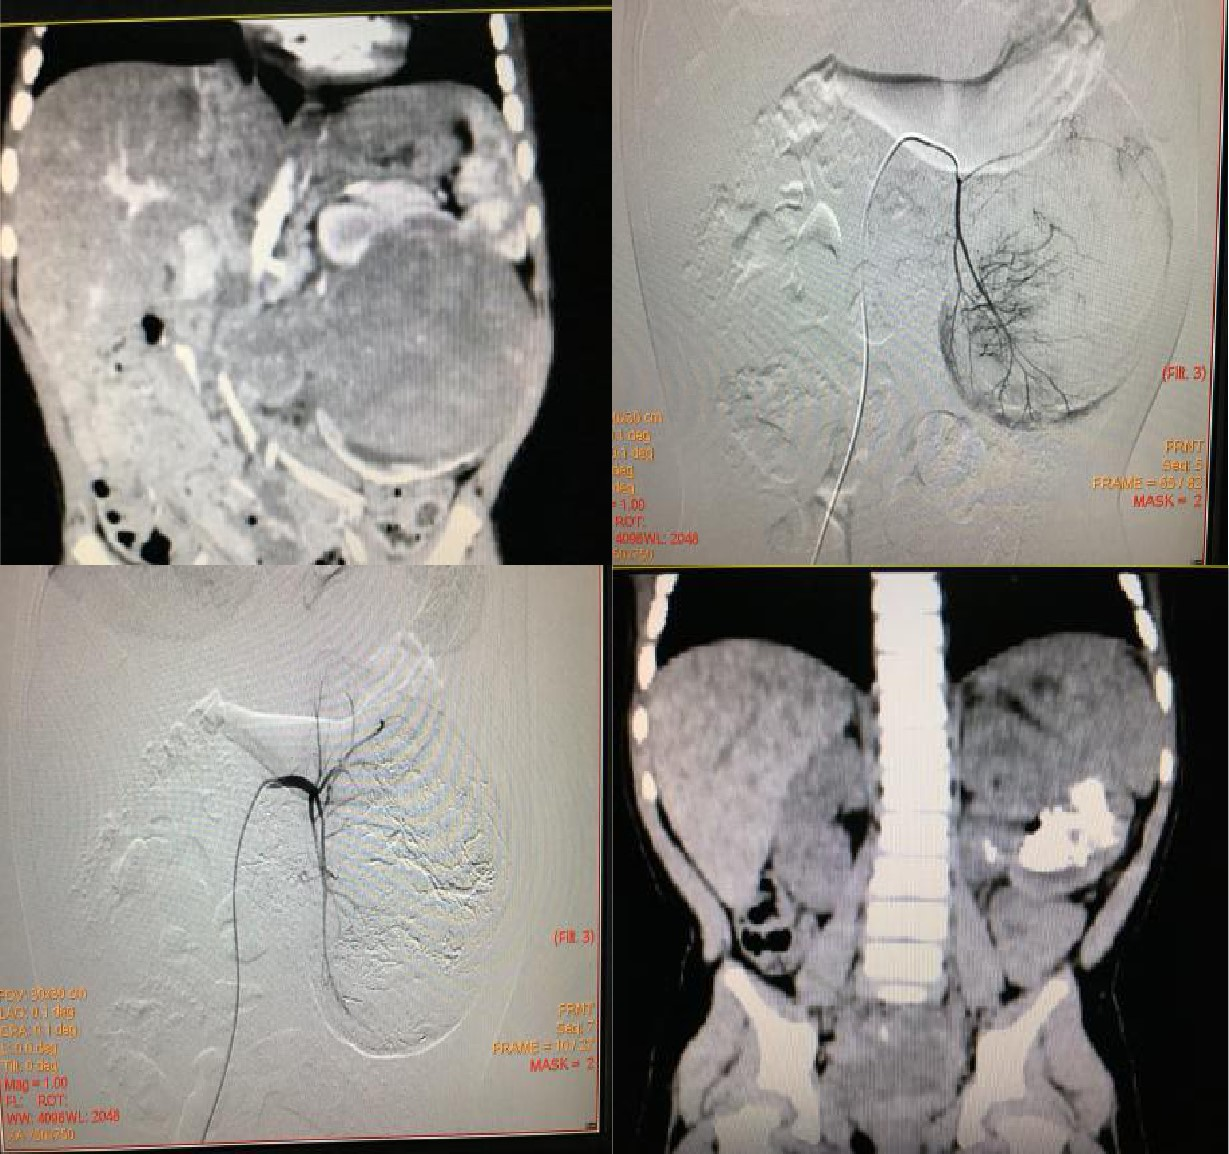

肝母细胞瘤化疗栓塞前后对比

肾母细胞瘤

肾母细胞瘤又称为Wilms tumor,是儿童最常见的腹部恶性肿瘤,在文献上称谓此瘤的名称多达80余个,反应出对该肿瘤认识过程的复杂性,其发病率在小儿腹部肿瘤中占首位。肿瘤主要发生在生后最初5年内,特别多见于2~4岁。左右侧发病数相近,3%~10%为双侧发病,或同时或相继发病。男女性别几无差别,但多数报告中男性稍多余女性。随着对肾母细胞瘤组织病理学检查及DNA含量测定的研究,并根据临床分期与病理类型所制定的治疗方案,肾母细胞瘤的治疗效果取得了惊人的进步。经肾动脉化疗栓塞术已经成为肾母细胞瘤重要治疗方案,特别是对局部向外侵犯或跨过中线的肾母细胞瘤,已经得到了广泛的认可,其技术已趋于成熟。同时,经肾动脉的化疗栓塞术可激活机体免疫机制来对抗肿瘤。经肾动脉化疗栓塞术治疗肾母细胞瘤的优势:1、经肾动脉化疗栓塞治疗肾母细胞瘤,化疗栓塞药物通过肾动脉直接作用于瘤体,明显优于全身化疗。2、目前普遍认为肾动脉的完全栓塞相当于先结扎肾动静脉,不仅可以减少肿瘤播散,而且由于阻断了肿瘤血供,可以造成肿瘤缺血坏死萎缩,病肾因梗死而水肿,与健康组织层次分明,曲张的肿瘤血管塌陷。3、对于巨大肾母细胞瘤,经肾动脉化疗栓塞后,瘤体明显缩小,可达80%以上。